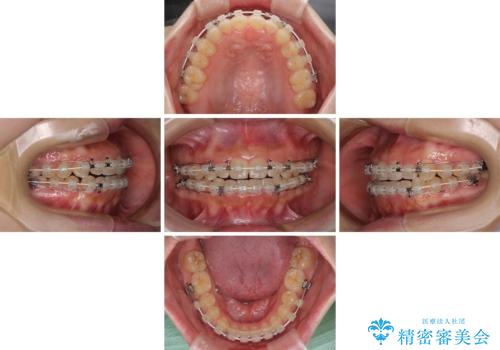

上顎骨を拡大したことで、下顎の歯列を上顎が受け入れられるようになりましたが、インビザラインでは咬み合わせを改善させることができなかったため、ワイヤー矯正にて仕上げることとしました。

ワイヤーを使用したものの、上下前歯のオープンバイトがなかなか改善されませんでしたが、患者希望により治療終了となりました。